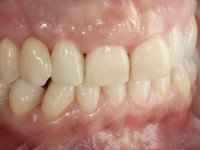

To define the dental zone to be covered by the Maryland bridge retainers, the patient was asked to perform maximum intercuspidation movements, and the contact points were marked with articular paper. Tooth preparation of the interproximal surfaces was made, to create a prosthetic insertion axis. It was sought that the mesio-distal diameter at the incisal level was equal to the diameter mesio-distal at the cervical level, that is to say, the interproximal walls were parallelized. Tooth preparation was done with fine grain diamond drills, and later polishing was done with abrasive discs. Color information was collected even before confection of the impression, to avoid dehydration of the arcade. Definitive impression was made using wash technique impression with silicone of heavy and regular consistency, both with fast setting, and a working plaster model was prepared in the lab. A laboratory scanner was used to scan the working model, and later, the infrastructure for the Maryland bridge was made using a CAD-CAM process. Ceramic was placed on this subframe. A ceramic adhesive was applied to the internal surface of the wings and connectors, which would enable bonding to the adjacent teeth. The adhesive bridge was bonded in the mouth following the conventional bonding technique. After bonding, the protrusion and laterality movements were carefully checked to avoid undesirable contacts.